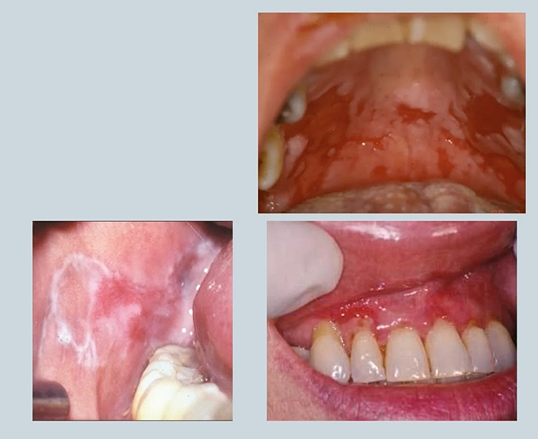

abnormalities in the oral mucosa- changes in colour - white 4

Candidosis (thrush)

Lichenoid lesion

Leukoplakia

Linea alba

Candidosis (thrush) - fungal infections - candida is commensal fungus but can overgrow. pseudomembranous - wipes off with gauze - debris - immunocompromised eg cancer treatments

Lichenoid lesion auto-immune - don’t come off on wiping - infiltration of lymphocytes → lichen planus, lupus

Leukoplakia smoking or immunosuppression - white patch of unknown aetiology - higher risks of turning into cancers

Linea alba -stress/anxiety - in line of occlusal plane - indentation of the cheek where you are biting - forms a thickened white area

abnormalities of the oral mucosa - changes in colour - red , examples 5

(severity of) Periodontitis – Diabetes, Cardiovascular disease

Mucous membrane pemphigoid – Autoimmune

Pemphigus Vulgaris – Autoimmune

Median Rhomboid Glossitis – Candida

Erythroplakia - Smoking

Median Rhomboid Glossitis – Candida - smoker or dry mouth

Erythroplakia (red patch) - Smoking but could be a pre cancer/cancer

textural changes in the oral mucosa 4

keratosis – White patches

Lichen planus

Lupus

Immunosuppression

Candidosis

Syphilis

hyperkeratosis - take a biopsy to make sure its not cancer